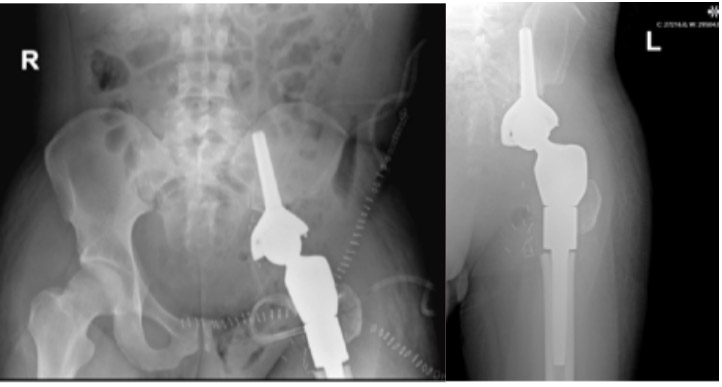

Post-surgery: The X-ray shows the prosthesis that was implanted after the tumor was removed.